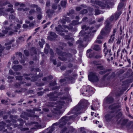

To deal with some of the aforementioned issues, we introduce a new approach for simultaneous H&E stain normalization and augmentation based on the multimarginal Wasserstein barycenter approach. Specifically, the novelty of the paper lies in first introducing the traditional Wasserstein barycenter approach for stain normalization/augmentation (Figure 1), and then introducing the multimarginal version [1, 9] to overcome the limitations of the traditional approach in this context (Figure 2). Note that the traditional Wasserstein barycenter (1 source and 1 reference), although widely employed in computer vision, to the best of our knowledge has never been used for stain normalization/augmentation and the more general multimarginal Wasserstein barycenter (1 source and multiple references) has hardly ever been used in computer vision or medical imaging communities. For more accurate stain normalization, the multimarginal version allows one to incorporate additional distributions by utilizing one or more intermediate reference images (Figure 2). The resultant interpolations span a broad spectrum of stain variations allowing for simultaneous stain normalization and augmentation.

We implemented our algorithm using the Python Optimal Transport (POT) library 222https://github.com/rflamary/POT which include GPU-accelerated versions of Sinkhorn regularization. We used Nvidia GeForce RTX 2080 Ti for our experiments. Pytorch framework was used for StainGAN 333https://github.com/xtarx/StainGAN and CNN3 444https://github.com/neerajkumarvaid/Nuclei_Segmentation implementations. We evaluated our approach against Reinhard et al. [12], Macenko et al.[7], Khan et al. [4], Vahadne et al. [17], and StainGAN [14].

4.1 Stain Normalization Evaluation

We used MITOS-ATYPIA’14 challenge dataset for evaluating our stain normalization. The dataset includes same tissue sections scanned by two different scanners (Aperio-A and Hamamatsu-H) with total 424 X20 A-H frame pairs, 300 training and 124 testing. Images from scanner A are normalized and matched against the real corresponding images from H (ground truth). As in StainGAN [14], 10,000 random (256256) patches from 300 training frames were used for training (26 epochs with the regularization parameter , learning rate 0.0002, Adam optimizer with a batch size of 4) and 500 patches from 124 testing data used for evaluation. The visual and quantitative comparisons are shown in Figure 3 and Table 1, respectively. For the traditional case (one reference and source), our results are very similar to Reinhard et al. [12] since they also do color matching in Lab space, but our results improve drastically given two reference images. The references in our case span patches with different amounts of background visible. We also tested with different reference images and we show that we get a tighter bound as long as the references contain different amounts of background visibility; see Figure 4 for the box plots of SSIM for different references.